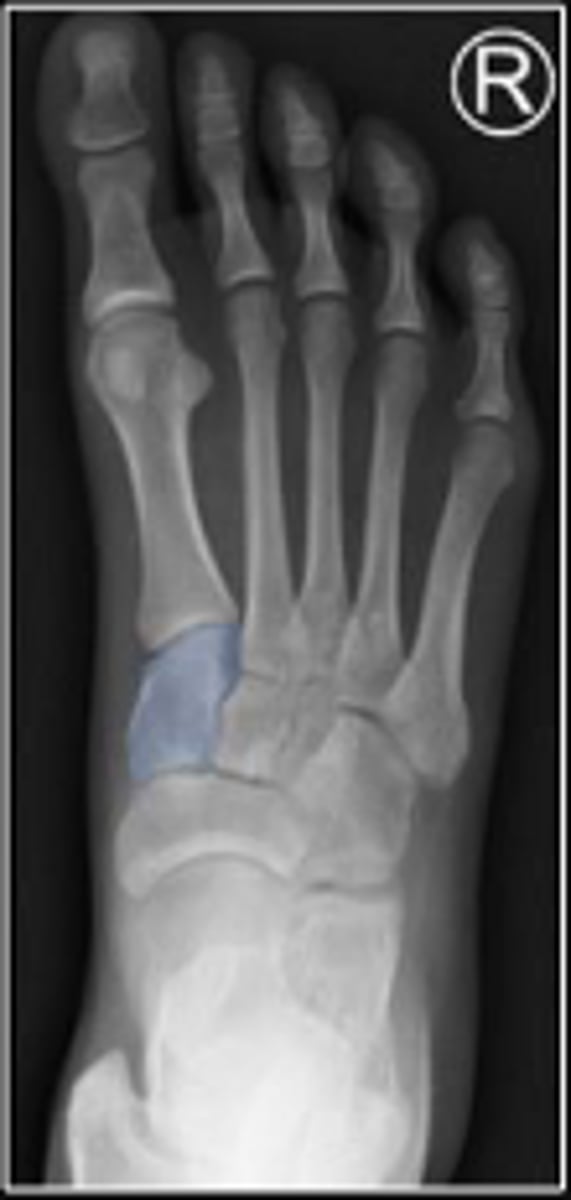

AP right foot

What is the name of the radiographic view?

Cuboid of the right foot

What are the arrows pointing to?

Medial cuneiform of the right foot

What is outlined?

2nd metatarsal of the right foot

Sesamoid bones of the right foot within the tendon of the flexor hallicus brevis

Medial sesamoid of the right foot within the tendon of the flexor hallicus brevis